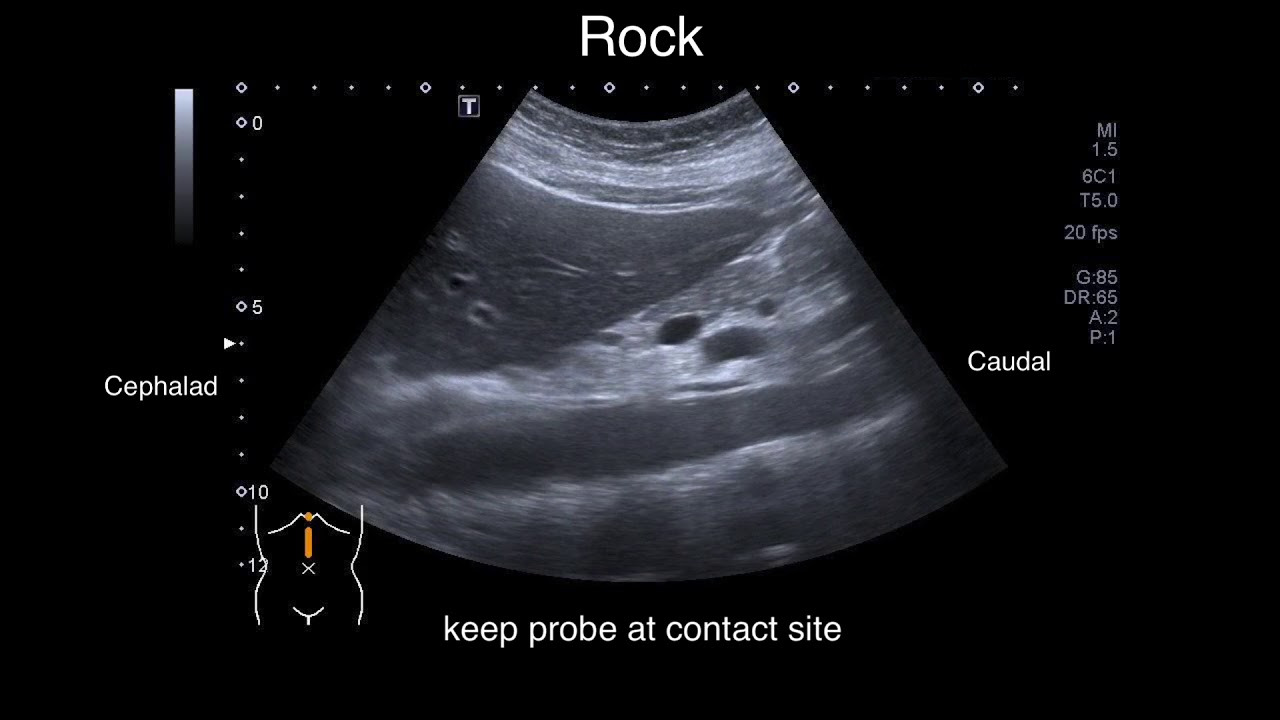

복부 초음파 검사는 인체의 복부 내 장기들을 실시간으로 확인할 수 있는 비침습적 영상 진단 방법입니다. 고주파 음파를 복부 피부에 쏘아 내부 장기의 반사 신호를 영상화하는 기술로, 내시경이나 CT와는 달리 방사선 노출 없이 안전하게 검사할 수 있다는 장점이 있습니다.

복부 초음파 검사 절차

- 검사 전 금식 안내 및 확인

- 초음파 젤을 복부에 도포

- 초음파 프로브(탐촉자)를 이용해 장기 확인

- 검사 중 환자의 자세 변경 요청 가능

- 검사는 약 10~20분 내외 소요

- 영상 촬영 후 의료진이 결과 판독

검사 중 통증은 없으며, 비침습적 방식이기 때문에 특별한 부작용이나 위험 없이 누구나 받을 수 있습니다.